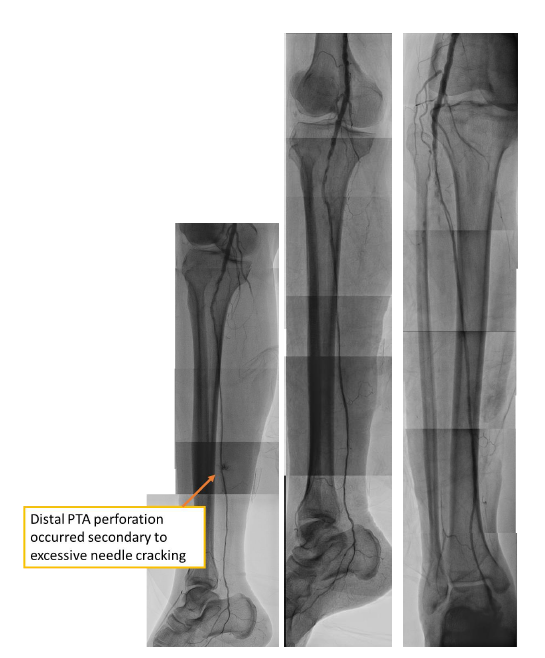

From a right femoral approach to RCFA, we used 0.014" GLADIUS GW with Oscar¢ç multifunctional peripheral catheter initially and changed wire to ASTATO XS40 GW to wiring the infrapopliteal CTO targeting the posterior tibial artery. However, even under strong support of Oscar¢ç multifunctional peripheral catheter, we still could not antegrade wiring through. Therefore, we performed a retrograde puncture to distal posterior tibial artery. We used 0.014" GLADIUS GW with CXI microcatheter and Knuckle technique to retrograde approach proximal posterior tibial artery. Successful rendezvous was achieved, confirming passage through the CTO segment. Balloon passage through the distal PTA lesion was difficult due to tight stenosis. So, several attempts with needle cracking technique on the distal PTA lesion was done, following serial balloon dilatation to PTA. Distal PTA perforation occurred secondary to excessive needle cracking. Several attempted hemostasis were performed following distal PTA perforation but in vain. A covered stent was deployed to seal the distal PTA perforation. Final angiography showed successful revascularization to PTA CTO.

This 75-year-old male patient suffered from chronic limb-threatening ischemia, resulting from proximal RSFA CTO. Successful recanalization of SFA and infrapopliteal CTOs often requires combined antegrade and retrograde wiring techniques. Wire rendezvous and retrograde tip-in are keys to crossing complex occlusions. Balloon passage in distal arteries can be challenging; small coronary balloons and needle cracking may help. Revascularization improves his wound healing and aids limb salvage. Nevertheless, prompt management of complications like arterial perforation with balloon tamponade, heparin reversal, and covered stents is vital